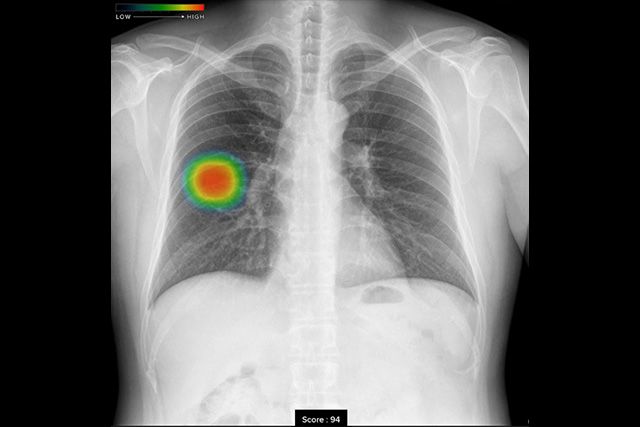

胸部X線画像病変検出ソフトウェア(CXR-AID)